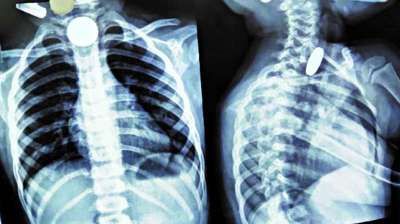

खिलौना नहीं सिक्का था! बच्चे ने निगले 5-10 रुपये के सिक्के, डॉक्टरों ने ऑपरेशन कर निकाले

24 Jul, 2025 04:09 PM IST | MPNEWSEXPRESS.COM

दिल्ली : दिल्ली के एक सरकारी अस्पताल के डॉक्टरों ने 12 वर्षीय बच्चे की जान बचाई है। बच्चे ने पांच और दस रुपये के तीन सिक्के निगल लिए थे। सिक्के...